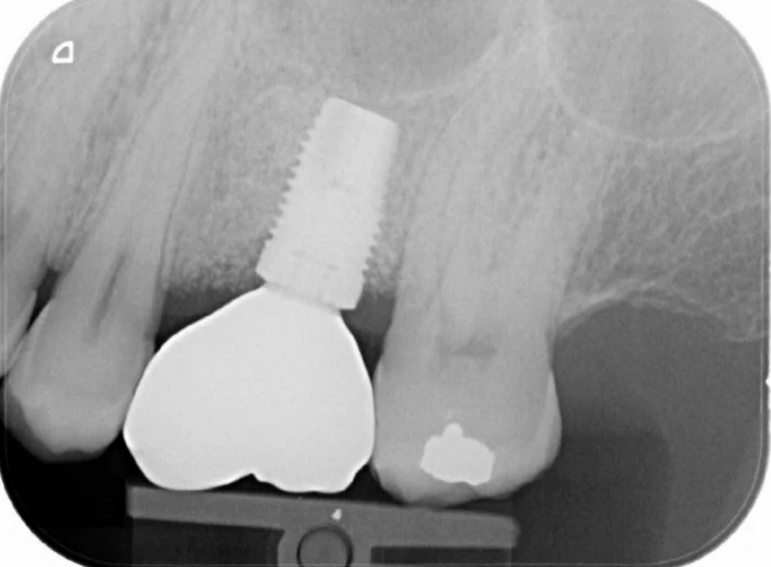

Case 12 – Implants

Molar with failed root filling replaced with an implant.